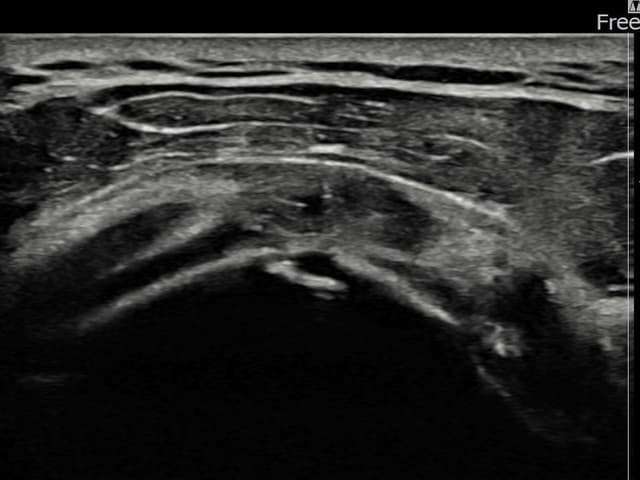

左侧 冈上肌腱 石灰化肌腱炎

9mm × 7mm